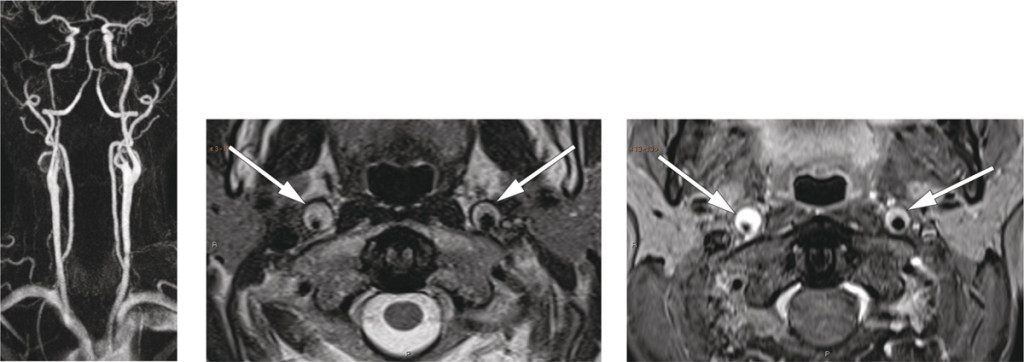

The neurological workup revealed Horner’s syndrome. CT angiography showed thickening of the walls of both internal carotid arteries, most pronounced on the right, from just above the bifurcation to the base of the skull. MR angiography and T2-weighted images confirmed bilateral carotid artery dissection, with a minimal lumen diameter of 2 mm on the right side (images to left and centre). Fat-suppressed T1-weighted images (right) showed high signal intensity in the arterial walls, consistent with intramural haematomas.